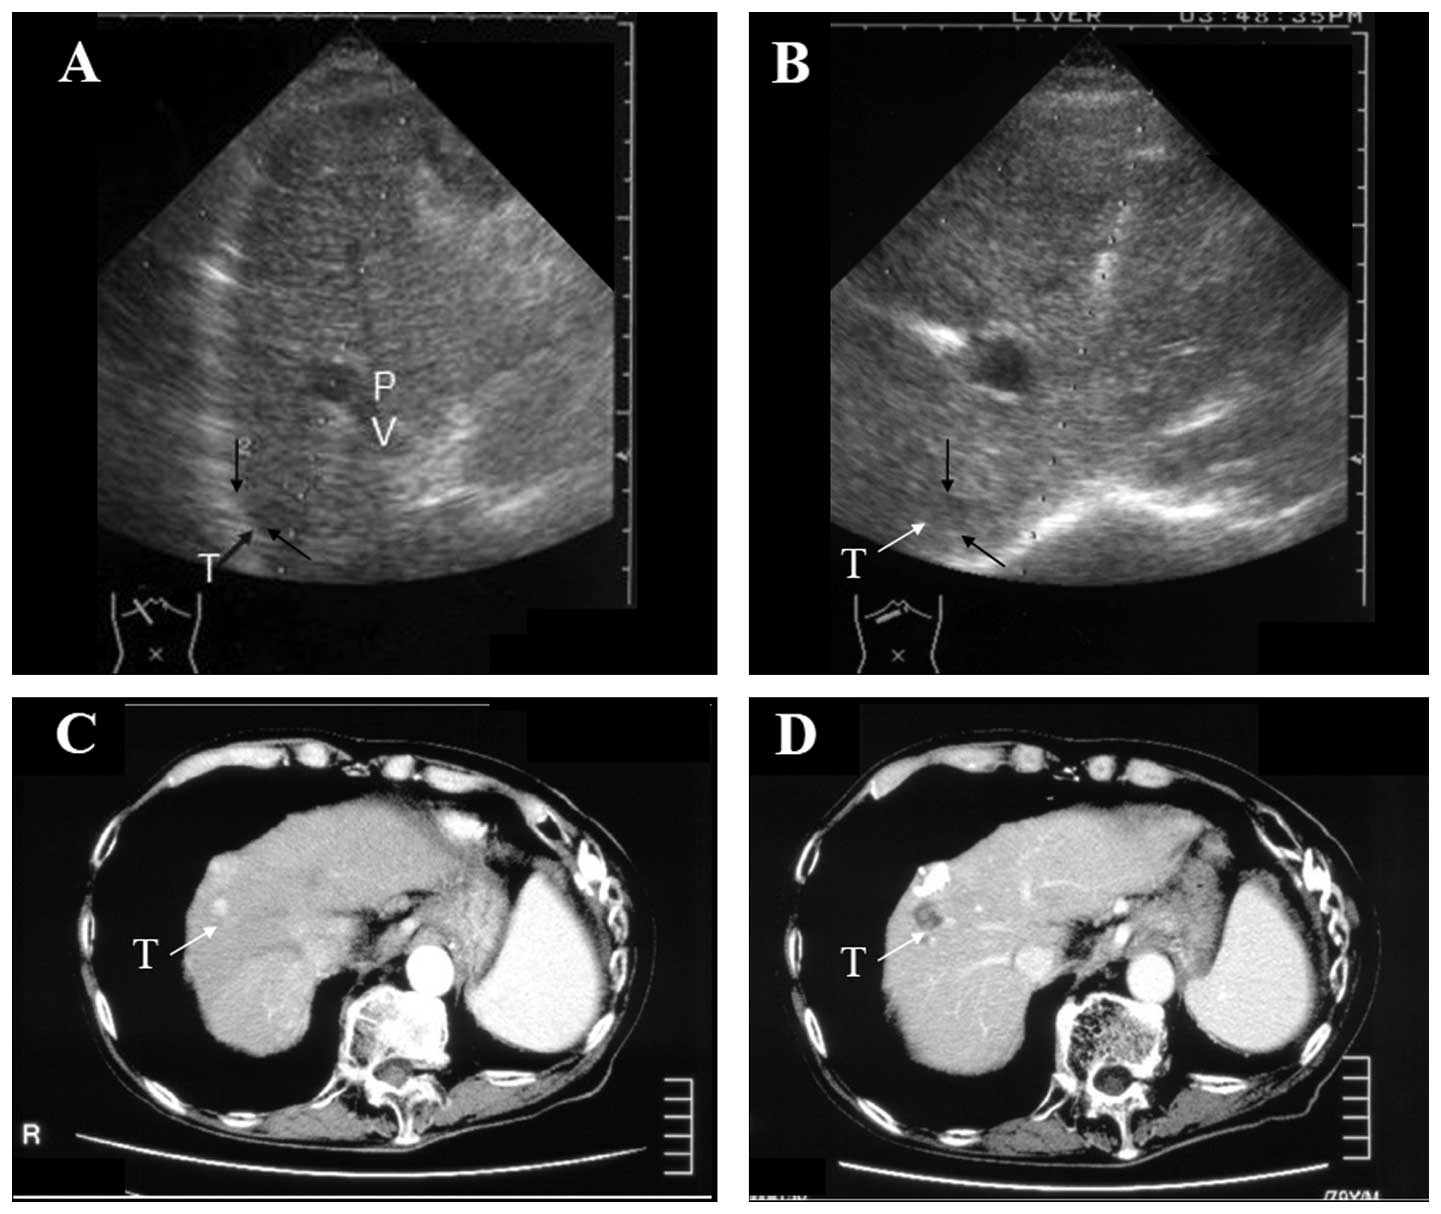

Ethanol injection therapy for small hepatocellular carcinomas located beneath a large vessel using a curved percutaneous ethanol injection therapy needle

Percutaneous ethanol injection therapy (PEIT) has been administered as a safe therapeutic modality for patients with small hepatocellular carcinoma (HCC). Due to the nature of the straight approaching line of a PEIT or radiofrequency ablation needle, penetrating the vessels that are interposed between the dermal insertion point and the nodule is unavoidable. A device with an overcoat needle and coaxial curved PEIT needle was created that facilitated a detour around interposing large vessels in order to avoid unnecessary harmful effects that result from the PEIT procedure. Two cases of HCC located adjacent to a neighboring large vessel were treated with a curved PEIT needle. The curved PEIT needle, which is connected to an outer needle, enabled deviation around the interposing vessels and successful connection with the HCC. Careful use of the curved line of the PEIT needle enabled the safe and successful performance of the PEIT without any requirement for specific training. This hand‑assisted technique may be an applicable treatment for small HCC located beneath large vessels as a direct therapeutic method using ultrasound guidance.

Figure 2